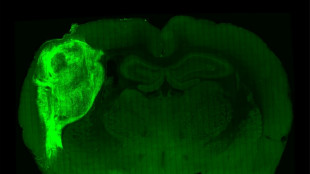

Implantan células del cerebro humano en ratas para estudiar desórdenes psiquiátricos

Un grupo de científicos implantó e integró con éxito células del cerebro humano en ratas recién nacidas, creando una nueva forma de estudiar enfermedades psiquiátricas como la esquizofrenia o el autismo.